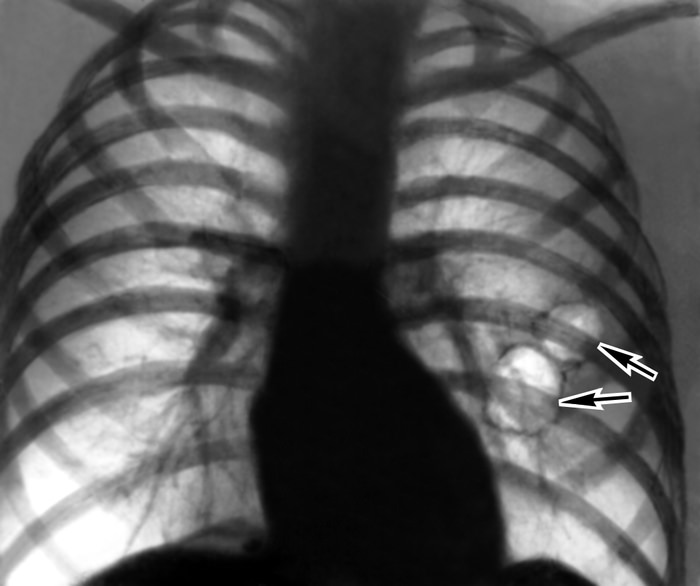

Для буллезной эмфиземы типично образование так называемых булл — воздушных пузырьков разного размера, концентрирующихся в основном в краевых отделах легких. Буллы могут быть множественными и единичными, локальными и распространенными, их размер варьирует от 1 до 10 см.

Фотографии эмфиземы

В историях болезни можно обнаружить интересные рентгеновские снимки, наглядно демонстрирующие патологическую картину эмфиземы легких. Отчетливо видны буллы при буллезной форме — в виде светлых округлых полостей. Обеднение сосудистого рисунка, уплощение диафрагмы, прозрачные легочные поля типичны для диффузных форм эмфиземы.